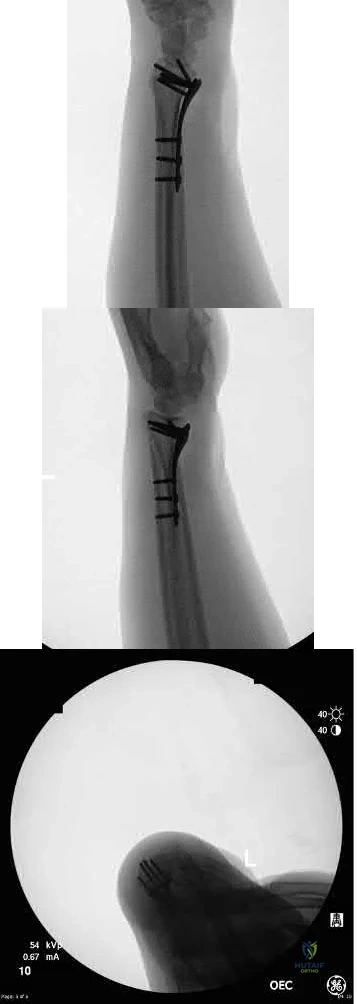

Figure A demonstrates a bicondylar tibial plateau fracture. Figure B demonstrates fixation of a tibial plateau fracture through a dual plating technique.

A 37-year-old male sustained the injury shown in figure A. He was treated with an intramedurally nail and a post-operative radiograph is shown in figure B. He underwent a post-operative CT Scanogram to assess for rotation. Figures C and D are of the operative side and Figures E and F are of the uninjured side. What is the version of the injured side and should any further procedures be undertaken for correction?